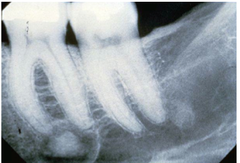

dentigerous cyst

-young adult -well defined unilocular radiolucency around crown of unerupted impacted or developing tooth